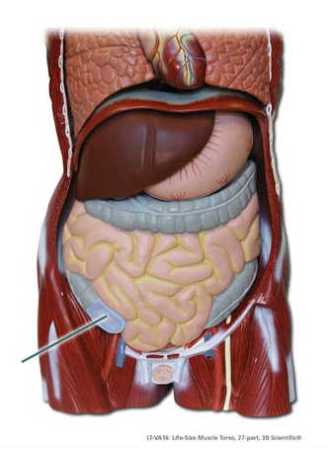

Identify the highlighted part of the large intestine.

cecum

Identify the highlighted structure.

stomach